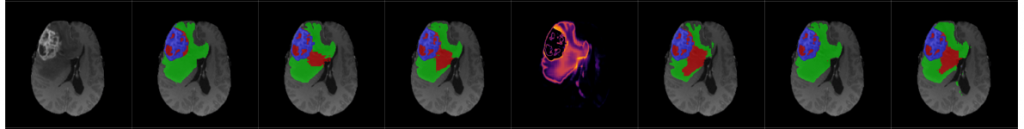

Robust image representations with counterfactual contrastive learning, Medical Image Analysis, 2025

A geometric approach to robust medical image segmentation, Medical Image Analysis, 2024